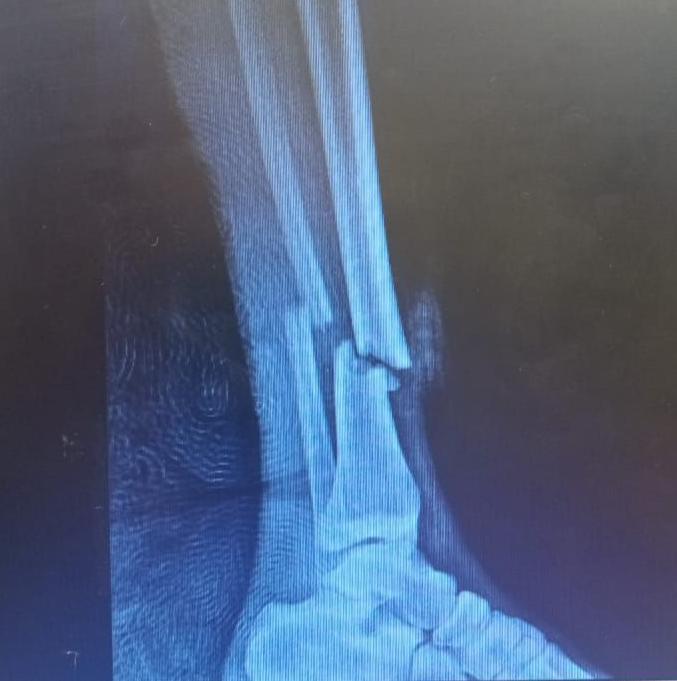

Por el impacto sufrió fractura expuesta de tibia y peroné. Viajará a La Plata donde este martes será intervenido. En sus redes agradeció el apoyo recibido. "Gracias a todos, estos mensajes hacen que todo sea más llevadero", dijo.